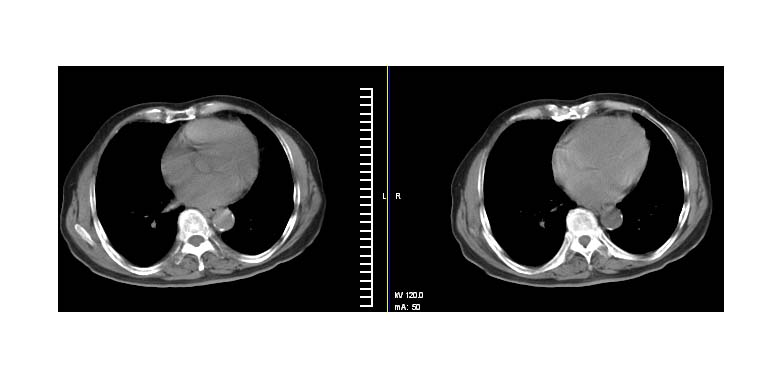

标题: CT11087:男性,82.咳嗽一周.抗炎治疗4-5天效果不明 [打印本页]

标题: CT11087:男性,82.咳嗽一周.抗炎治疗4-5天效果不明

考虑左上肺癌,似与左侧肋骨关系密切?

左上肺实质性肿块,浅分叶 毛糙 胸膜凹陷征 纵隔淋巴结肿大——支持:左肺上叶周围型肺癌!

左上肺软组织肿块,有分叶,短毛刺,气管旁间隙见有肿大淋巴结,考虑左上周围型肺癌伴纵隔淋巴结转移。